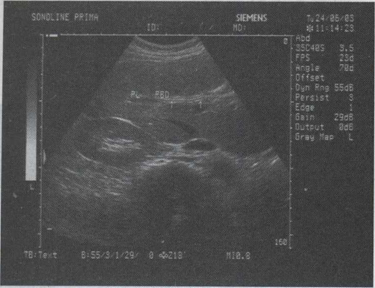

34.女,34岁,经常反复发作剧烈的右上腹痛,加重1天,声像图如图所示,最可能的诊断为()